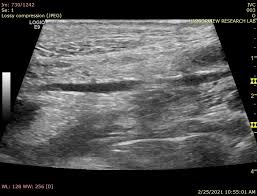

복부 초음파는 비침습적이며 방사선 노출이 없는 안전한 검사 방법으로, 초음파(ultrasound)를 통해 복부 내 장기들의 상태를 실시간으로 확인할 수 있는 진단 도구입니다. 복부 초음파로 알 수 있는 것 중에서는 특히 간, 담낭, 췌장, 비장, 신장, 방광, 대동맥, 소장, 대장 등의 상태를 파악할 수 있으며, 질환의 조기 발견에 탁월한 효과를 보입니다.

- 젤 도포: 초음파 탐촉자와 피부 접촉 향상을 위해 복부에 젤을 바름

- 탐색: 탐촉자를 위·아래·양옆으로 이동하며 각 장기를 촬영

- 체위 변화: 장기 위치에 따라 옆으로 눕거나 숨을 들이쉬게 요청